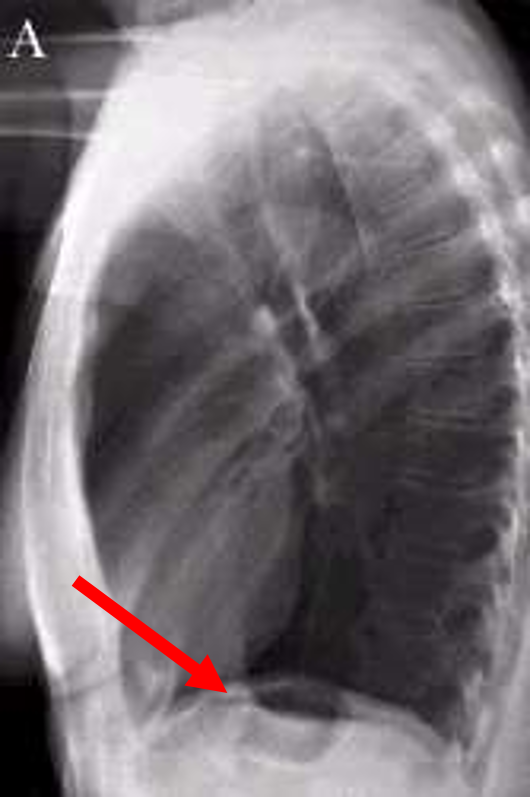

what lateral view would you get for a left sided lesion

a left lateral view

three rules of a lateral chest x ray

diaphragm shadow

retrosternal space

retrocardiac space

lateral chest

what is this? when would you take this?

expiratory AP

looking for pneumothorax

aortic arch

pulmonary artery